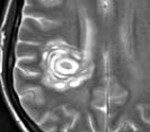

G37.5 Концентрический склероз [Бало]